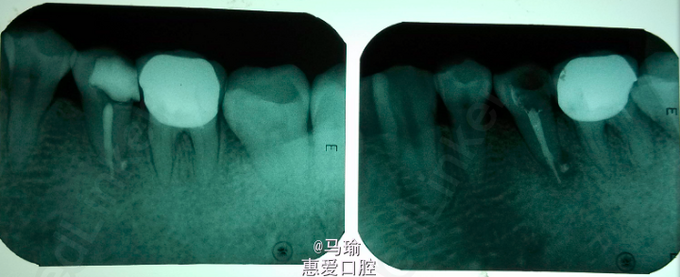

检查:35牙远中邻合面龋坏,龋坏较深,已穿髓,探(-),冷(-),叩(++),I度松动,唇颊侧未见明显瘘道。 x线片示35牙远中邻合面牙体组织密度减低影,与髓腔相通,根尖周组织暗影,根尖1/4处疑似根折,远中暗影。

诊断:1、35牙慢性根尖周炎 2、35牙根折? 治疗计划: 1、35牙根管治疗+树脂充填+冠修复 2、35牙拔除 处置:治疗前告知患者35牙可能存在根折,需要根尖外科手术或拔除等其他治疗,患者知情同意。 常规根管扩挫,根测仪可测得根管长度,试尖可,封药后预约复诊。 患者复诊时无不适,遂行根管充填,拍片后意外发现疑似根折的地方有糊剂溢出,磷酸锌暂封,嘱患者3月后复诊。

3月后患者复诊,x线片示根尖周暗影减少,患者无不适,遂行树脂充填,嘱患者修复科冠修复。 讨论:这种侧支根管的暗影特别像根折,会影响医生的判断,且与根尖周炎的症状有相同之处,因此不太能区分,只有在做的过程中去判断,不过事先得向患者说明情况。不知大家有没有遇到过这种情况?